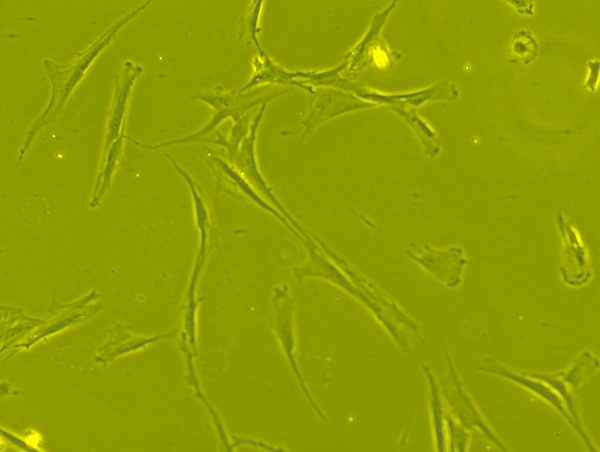

Conversion of Mesenchymal Stem Cells to Cancer-Associated Fibroblasts in a Tumor Microenvironment: An in vitro Study

Conversion of Mesenchymal Stem Cells to Cancer-Associated Fibroblasts in a Tumor Microenvironment: An <em>in vitro</em> Study

Mesenchymal stem cells(MSCs) play a role in tumor formation by differentiating into cancer associated fibroblasts (CAFs) which enable metastasis of tumors. The process of conversion of MSCs into CAFs is not clear. In this study, authors tested the hypothesis that cancers cells secrete soluble factors that induce differentiation by culturing bone marrow mesenchymal stem cells in media conditioned by a breast cancer cell line.